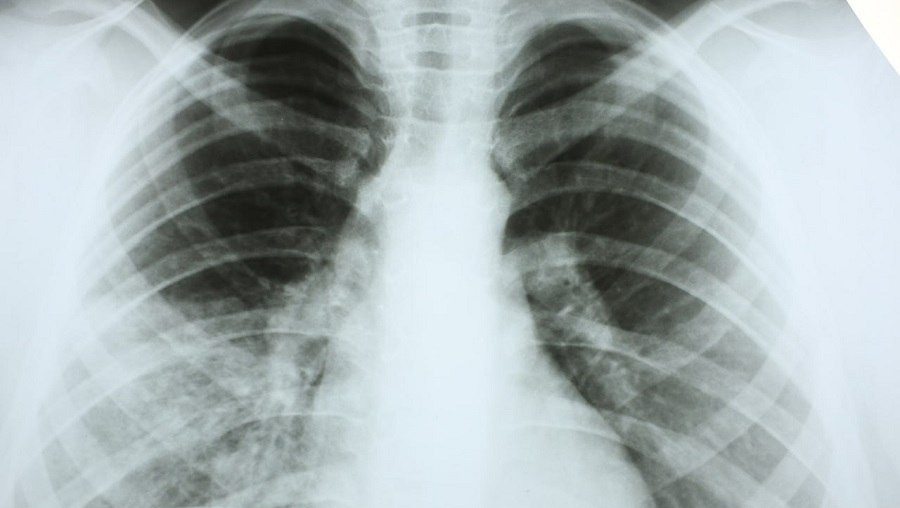

Пневмония – это острое инфекционное заболевание, различной этиологии (преимущественно вирусно-бактериальной), характеризующееся поражением лёгких, интоксикацией, респираторными нарушениями, специфическими физикальными данными и инфильтрацией на рентгенограмме грудной клетки.

Заболевание может начинаться как острая респираторная вирусная инфекция (ОРВИ), без кашля. Если пневмония вызвана вирусом, врач не всегда может её прослушать. Для точного подтверждения диагноза необходимо сделать рентген грудной клетки.